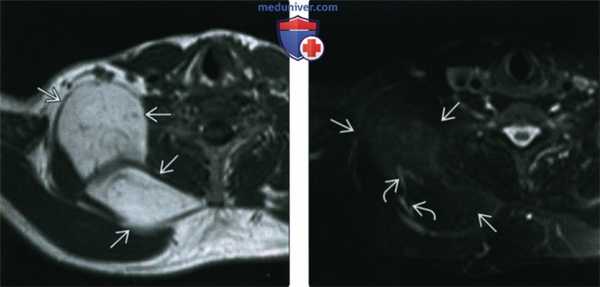

(Слева) МРТТ1 ВИ, аксиальная проекция. Пациент 53 лет с липосаркомой копчика в анамнезе. У пациента имеется дольчатое образование В в области плеча, в правой надключичной и околопозвоночной областях. Сигнал гиперинтенсивный.

(Справа) MPT T2BИ FS, аксиальная проекция. Практически полное подавление сигнала от образования. Сосуды в образовании имеют нормальное строение. Накопления гадолиния или других данных, говорящих в пользу саркомы, нет. Удаленная опухоль оказалась доброкачественной липомой.